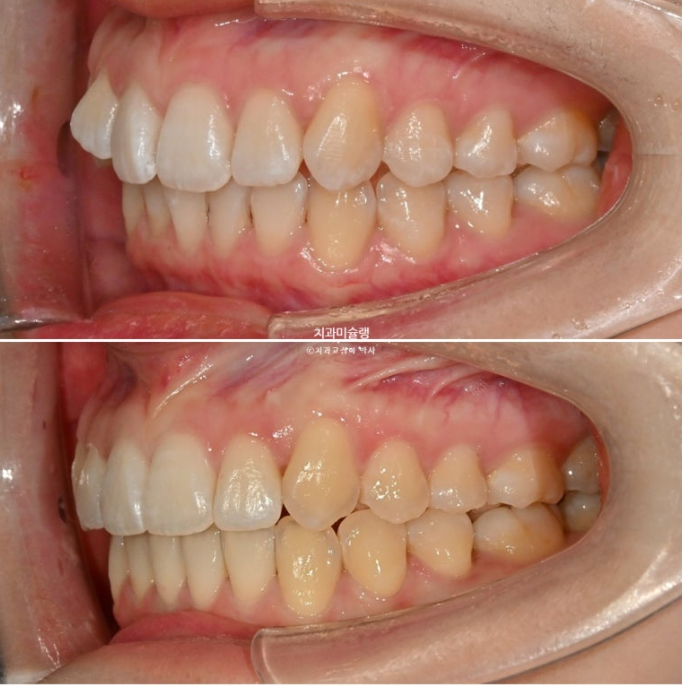

2급 교합관계를 보이는 좌측엔 교합관계 개선을 위한 악간고무줄 처방을 해서 덧니뿐아니라 교합관계개선과 주심선 개선을 도모합니다.

고무줄을 열심히 껴준 탓에 좌측 교홥관계는 좀 더 1급에 가까워졌습니다.

25.01~25.11

우측은 완벽한 1급을 달성했습니다